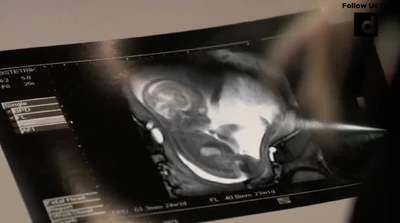

"Misha" admire their newborn, Daisy (2025)

As Michael was away receiving burn treatment in Germany, Sasha went through most of the pregnancy alone, but with support from Michael's uncle Jason Morgan, the Quartermaine's and the Scorpio's. She would occasionally send sonogram photos to Michael in Germany. Michael returns to Port Charles after his stint at the Baden-Baden Clinic for his burn treatment, during the 2025 Nurses' Ball, to the shock and surprise of everyone, especially Sasha. Sasha was reunited with Michael and Wiley at his mother's house with Amelia.

On April 18, Jason accompanies Sasha as she gets her ultrasound and seems moved to see the baby. Afterward, Sasha is thrilled as the baby is almost developed. Jason asks if he can send one of the photos to Michael, which prompts Sasha to ask why. He thought it would help his recovery to see that she and the baby are healthy. Sasha asks to think about it, as she doesn't want Michael any more involved than he has to be. She thanks Jason for coming today, though.